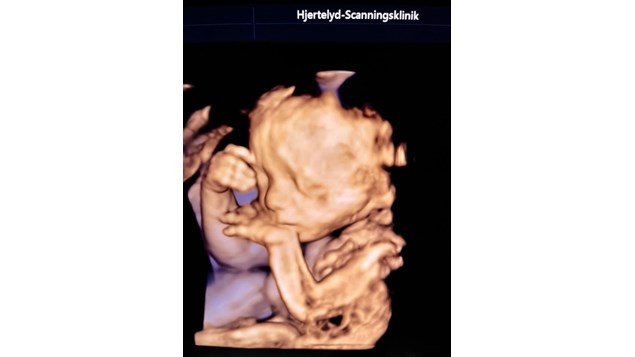

Sød lille dreng på besøg helt fra Dragør Han gav stjernestunder til både mor, mormor og oldemor, der aldrig havde oplevet ultralyd før i en alder af 91. TAK for godt samarbejde bette mand DU var en stjerne